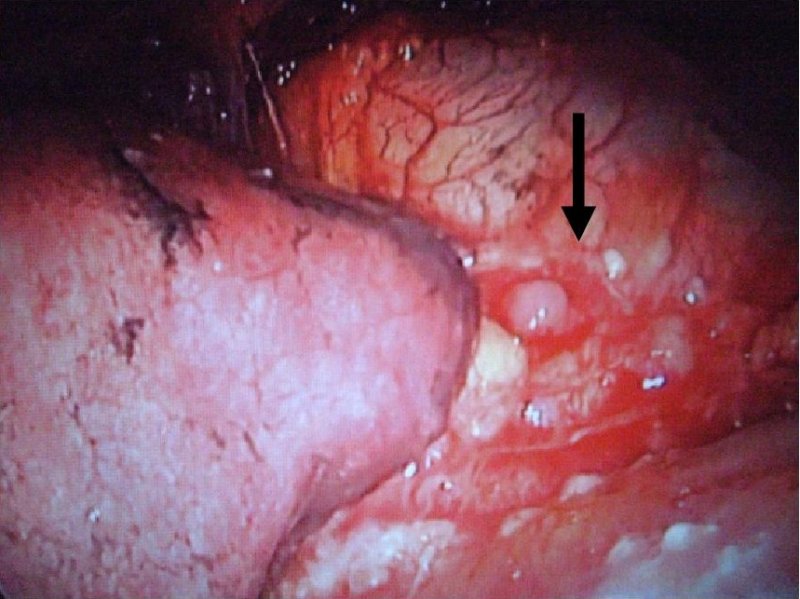

自然気胸の術中所見

肺嚢胞からの空気漏れ

肺嚢胞の結紮